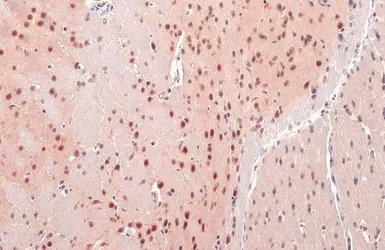

O-GlcNAc transferase antibody detects O-GlcNAc transferase protein at cytoplasm and nucleus by immunohistochemical analysis.

Sample: Paraffin-embedded rat brain.

O-GlcNAc transferase stained by O-GlcNAc transferase antibody (GTX109939) diluted at 1:500.

Antigen Retrieval: Citrate buffer, pH 6.0, 15 min